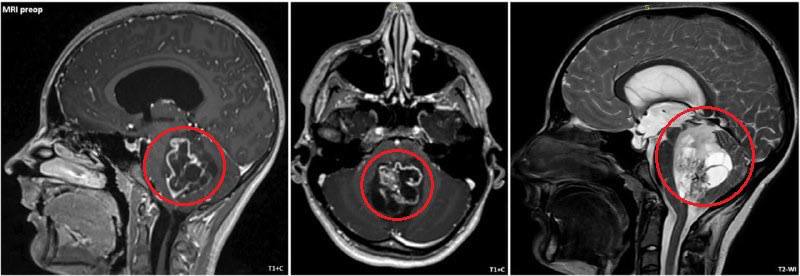

Врачи Детского клинического центра имени Льва Рошаля провели сложнейшую операцию 15-летнему пациенту. У подростка диагностировали опухоль задней черепной ямки размером около 5 см, из-за которой его постоянно тошнило и рвало.

Хирурги во главе с Асланом Текоевым удалили образование с помощью ультразвукового аспиратора, сохранив все жизненно важные структуры мозга. Сейчас подросток чувствует себя хорошо и уже выписан из больницы.